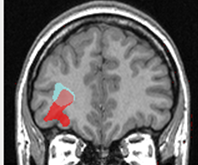

The analysis of neuroimaging data such as magnetic resonance imaging (MRI) and positron emission tomography (PET) is increasingly used in the pre-surgical work-up of patients suffering from epilepsy and may offer an alternative to the invasive reference of Stereo-electro-encephalography (SEEG) monitoring. Integrating the large amount of visual information provided by the multiparametric and multimodality data, however, is complex, especially for junior neurologists with less expertise.

To assist clinicians in screening these lesions, we developed a computer aided diagnosis system (CAD) based on a multivariate data analysis approach. Our first contribution was to formulate the problem of epileptogenic lesion detection as an outlier detection problem. The main motivation for this formulation was to avoid the dependence on labelled data and the class imbalance inherent to this detection task. The proposed system builded upon the one class support vector machines (OC-SVM) classifier. OC-SVM was trained using features extracted from MRI scans of healthy control subjects, allowing a voxelwise assessment of the deviation of a test subject pattern from the learned patterns. System performance was evaluated using realistic simulations of challenging detection tasks as well as clinical data of patients with intractable epilepsy.